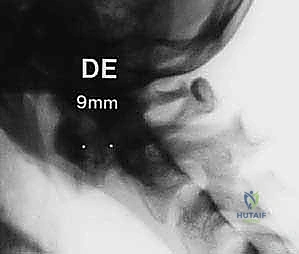

* Anterior atlantodental interval (AADI) greater than 3.5 mm in an adult indicates potential transverse ligament damage. An AADI > 5 mm indicates probable injury to both transverse and accessory ligaments. This is a strong indication for C1-C2 arthrodesis in a trauma setting.

FIG 2 • A. An anterior atlantodental interval greater than 5 mm indicates likely injury to the transverse ligament and, in the setting of trauma, necessitates operative stabilization.